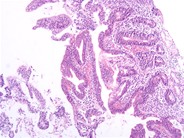

A 70-year-old Hispanic woman with history of coronary arterial disease presented with dull abdominal pain and weight loss for ∼2 weeks. A computed tomography scan of the abdomen revealed a large mass occupying the proximal jejunum. The patient had no history of celiac disease or malabsorption. She underwent surgical resection. Grossly, the tumor measured 10 cm in length and had a multinodular appearance with surface ulceration and a soft “fish flesh,” yellow-white, homogenous cut surface (panel A). Microscopically, the tumor consisted of monomorphic small lymphocytes (panel B) positive for cytoplasmic CD3, CD8, CD56, and T-cell receptor γ (TCR-γ), and negative for CD4, CD20, CD30, and TCR-β.Enteropathy-associated T-cell lymphoma (EATL) is a lymphoma of intestinal intraepithelial T lymphocytes. The World Health Organization divided EATL into 2 variants: a classical form (type I), which comprises 80% to 90% of cases, and a type II or monomorphic variant, which comprises 10% to 20% of EATL cases. The classical form consists of large pleomorphic lymphoma cells which are usually CD3 +, CD5 −, CD7 +, CD8 −/+, CD4 −, CD56 −, TCRβ +/−. Type II is composed of small round monomorphic cells. The tumor cells in type II are CD3 +, CD4 −, CD8 +, CD56 +, and TCRβ +. Type I is mostly associated with celiac disease. The monomorphic variant may also be preceded by celiac disease but it has not been well characterized.